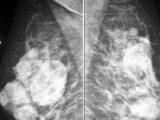

Os diagnóstico por imagem do exame são realizados com equipamentos de Raios-X, Tomografia Computadorizada, Ressonância Magnética, Ultrassonografia.

No planejamento radioterápico são usados exames de diagnóstico por imagem, como raios-x, tomografia e ressonância magnética, para se saber o tamanho e localização do tumor.